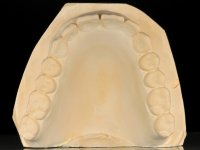

Two dental implants were planned in the CBCT scan, in the area of the inferior canines. The dental extractions were performed and, simultaneously, the alveolar crest was flattened and the implants were placed. Three issues were considered while implant placement: parallelism of the axis, same height of the implant’s neck, and same position in the coronal plan. This 3D insertion is essential to have a good retention of the overdenture in the future. Patient’s removable denture was fixed in the dental lab, to include the extracted teeth, and a soft-tissue relining was done over the healing abutments. After the osseo-integration period, a first impression was done with an open-tray and a doble-mix technique. This dental impression allowed the production of screwed wax-rims and an individual tray for a functional impression. A second impression, final, was done with an individual tray with a monophasic silicone. The occlusal wax-rims were correct in the mouth according to the full denture guidelines. Special care was taken with the occlusal vertical dimension and the support in the soft-tissues. A silicone bite registration material was used to better defined the intermaxillary relations. Teeth set-up was done in the dental lab with the selected tooth color. Due to the fact that the base was screwed to the dental implants, the teeth set-up was functionally evaluated in the mouth. Another silicone bite registration material was used to allow final occlusal adjustments. Finally, the locators were screwed and the retention nylons were selected according to the patient needs.